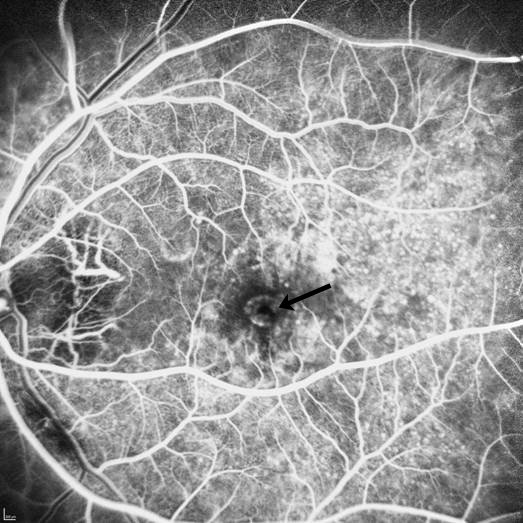

Abbildung 6: In dieser Angiographie sieht man wieder das Auge des Patienten aus den Abb. 3-5. Hier sind die Gefäße mit einem Farbstoff (Fluoreszein-Natrium) sichtbar gemacht. In der Netzhautmitte (Sehgrube) sieht man normalerweise keine Anfärbung mit Farbstoff. Die Gefäßneubildung, die zu der Sehminderung bei unserem Patienten geführt hat, stellt sich durch eine Farbstoffanreicherung (Pfeil) dar.

Abbildung 7: Die Abbildung 7 unseres Patienten (siehe Abb. 3-6) zeigt in der sogenannten Spätphase des Angiogrammes (5 Minuten nach der Injektion des Farbstoffes), dass der Farbstoffaustritt im Bereich der Gefäßplatte (Pfeil) zugenommen hat. Dies beweist die Minderwertigkeit dieser Gefäße mit Austritt von Flüssigkeit unter die Netzhautmitte, Verdickung der Netzhaut und damit Funktionseinschränkung.